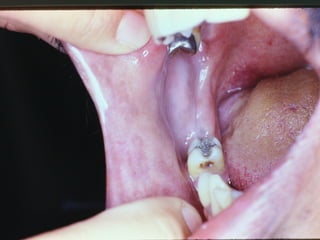

Tatuagem por Amalgama

• Impregnação

• Áreas de Abrasão na Mucosa

• Fragmentos em Área de Extração

• Aspectos Clínicos Radiográficos